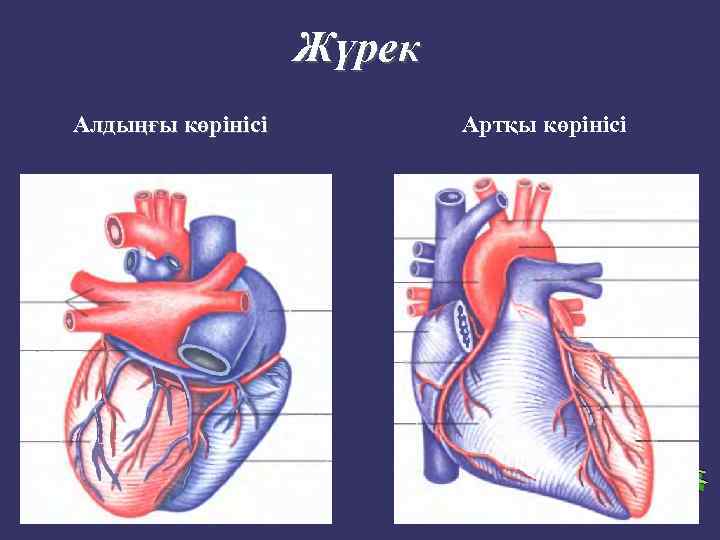

Жүрек Алдыңғы көрінісі Артқы көрінісі

➲ ➲ ➲ Зерттеу барысында жүрек камераларының кеуде қабырғасына жатқызылуын елестетіп алуымыз керек. Оң жақ қарынша жүректің алдыңғы беткейінде орналасады. Бұл камера өкпе артериясымен кеуденің сол және артқы жағында сына тәрізді жазықтықты құрастырады. Оң жақ қарыншаның төменгі бөлігі кеуде денесінің төстің семсер тәрізді өсіндісімен байланысқан жерінен төмендеу орналасқан. Оң жақ қарынша жоғарыға қарай тарылады және III- қабырға мен төстің арасындағы шеміршек деңгейінде өкпе артериясына өтеді. Сол жақ қарынша оң жақ қарыншадан солға және артқа қарай орналасқан. Жүректің алдыңғы беткейінің кіші бөлігін ғана алып жатады. Клиникалық жағынан бұл өте маңызды, өйткені ол жұректің сол жақ бөлігін құрайды және жоғарғы серпілістің негізгі көзі болып табылады. Жоғарғы серпіліс бұл жүректің систола кезінде кеуде қабырғасына соғуын сипатайды және V қабырға арасында болады.